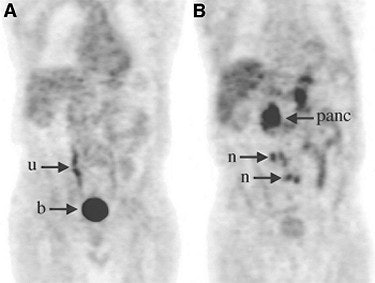

| Above, a 77-year-old man with PSA relapse and a serum PSA value of 10.5 ng/mL. The patient underwent radical prostatectomy and salvage external-beam radiation. The coronal FDG-PET image (A) showed only urinary activity in the right ureter (u) and bladder (b). The AC-PET (B) image indicates high uptake in the multiple paraortic lymph nodes (n), and normal uptake in the pancreas (panc). Image and caption courtesy of Dr. Nobuyuki Oyama and the Journal of Nuclear Medicine. |